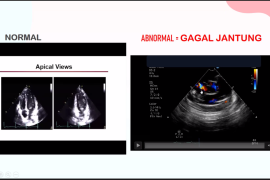

Jakarta (ANTARA) - Dokter dari Perhimpunan Dokter Spesialis Kardiovaskular Indonesia (PERKI) dr. Rarsari Soerarso, SpJP(K) mengatakan gejala sesak napas pada kardiomiopati peripartum (PPCM) atau gagal jantung pada akhir masa kehamilan umumnya sulit dikenali.

Menurut PERKI, PPCM merupakan gagal jantung akibat disfungsi sistolik dengan fraksi ejeksi ventrikel kiri (FEVK) kurang dari 45 persen tanpa penyebab yang reversibel pada akhir masa kehamilan hingga beberapa bulan pasca-persalinan, pada perempuan yang sebelumnya diketahui tidak menderita penyakit jantung.